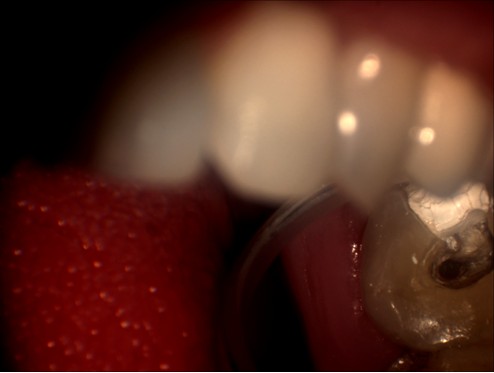

明美工程師在剛開始接觸牙科專用顯微鏡時,對這臺牙科專用顯微鏡有點陌生。牙科專用顯微鏡與其他的顯微鏡有點不同,1米多高的機身,沒有粗微調(diào),調(diào)焦只能通過手動上下移動來實行。在安裝過程中遇到了很多技術(shù)上的難題,如顯微鏡的接口問題,這款顯微鏡的C接口并不是標(biāo)準(zhǔn)的C型接口,有點偏小。經(jīng)過我們工程師專業(yè)的技術(shù)經(jīng)驗及反復(fù)試驗,發(fā)現(xiàn)在它原有的接口的基礎(chǔ)上再接上準(zhǔn)的C型接口,即接兩個C接口就能把顯微鏡相機安接裝上去。但是安裝上去并不能完解決此問題,還有成像方面的問題,由于它原有的C接口不是標(biāo)準(zhǔn)的C口,在實拍的時候,可以達到同步的效果,而且靜態(tài)拍攝圖片效果不錯,但在實際口腔內(nèi)拍攝的時候圖像太暗,若只通過軟件調(diào)節(jié)后,亮度達到了,但是有點反光,通過和技術(shù)人員溝通后,發(fā)現(xiàn)那臺顯微鏡用的是一個普通的照明燈,亮度不可調(diào),通過幾番周折后,通過調(diào)試后亮度問題終于解決。明美工程師在順利安裝完成了,楊主任對此效果表示滿意,亦對明美工程師的專業(yè)技術(shù)能力給予肯定。以下為顯微鏡相機實拍圖片:

顯微圖片

牙科顯微圖片